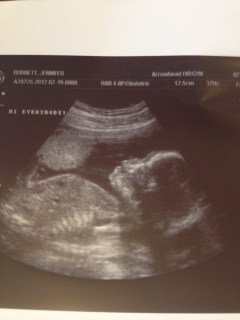

Also we had our check up for the month this week and got to see all of Baby Jenkins. I would say little but apparently he’s not so little. He is measuring about a week ahead and it looks to us like his head is not small. As Brad said, he has a big brain like his daddy, haha. I am excited cause I would love for him to show up early, say… Thanksgiving. Brad is rooting for 12/12/12. I’m guessing we will start places bets when it get a little closer.

| This is Baby Jenkins at 20w and 4d. It was taken this morning in between his wiggling! |